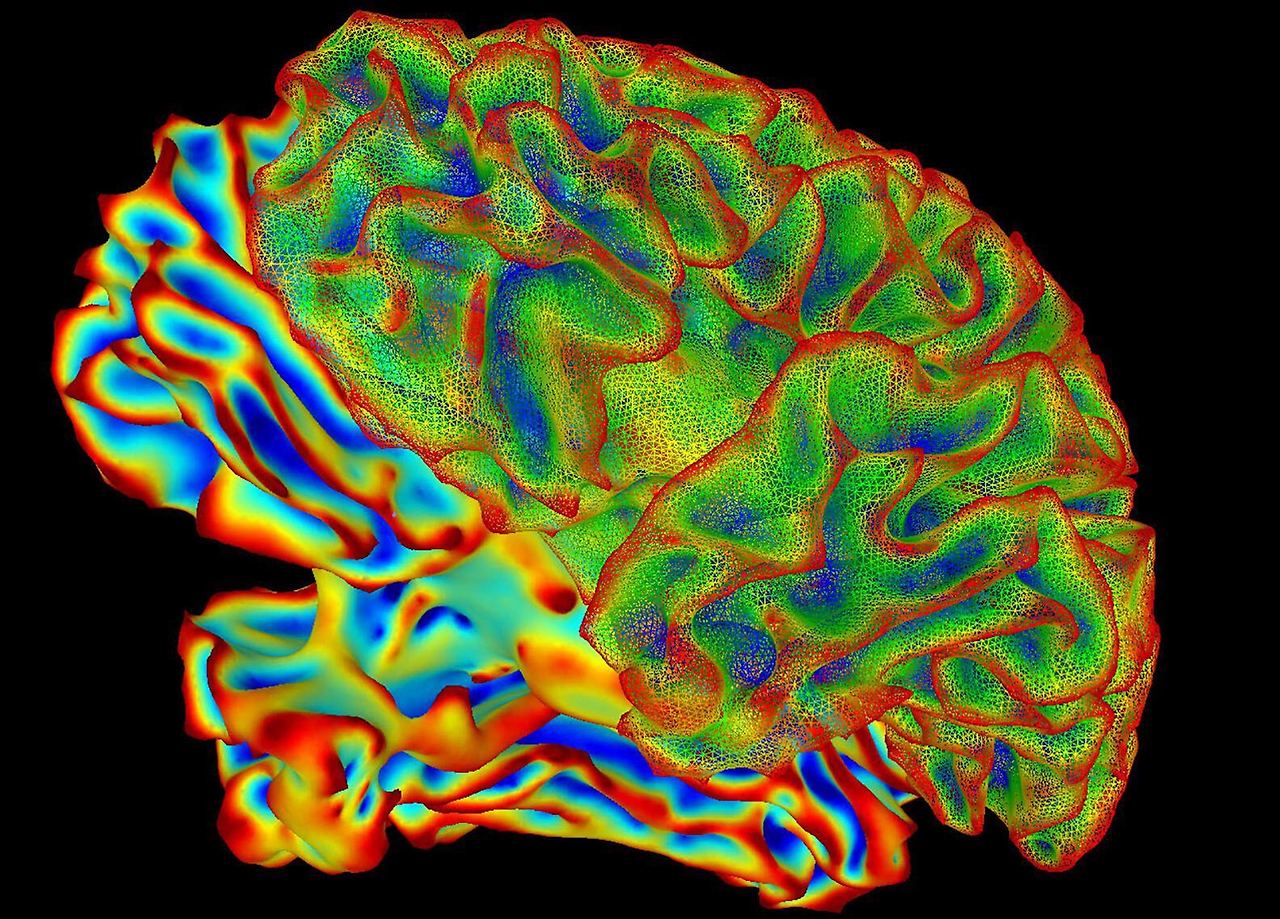

- 참가자들에게 짧은 영상(물체, 장면, 행동 등을 담은)을 보여주며 기능적 자기공명영상(fMRI)(fMRI)으로 뇌 활동을 스캔. Medical Xpress+1

- 스캔된 뇌 신호 데이터를 AI 모델이 해독해, 그 사람이 보고 느낀 내용을 텍스트 문장으로 생성하는 방식. Medical Xpress